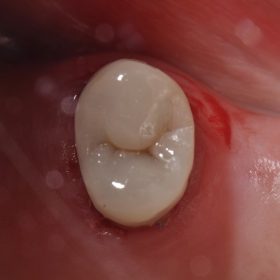

Large Cavities and Invisible Fillings | Cosmetic Dentistry Auckland

Class II’s and Essentia U – a pair made in heaven. A very eager chameleon effect allows for minimization of your restorative material armamentarium. See you guys in Sydney for […]

Composite Filling Artistry | Aesthetic Dentistry | Anatomic Restorations | Dentist Auckland

Hello! Tooth 15 suffered from a cracked isthmus and deep recurrent caries along with biting sensitivity on the restoration. The Garrison Compositight 3D Fusion was utilized to reconstruct a firm, […]